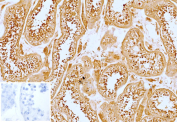

Immunohistochemistry of DR3 Ligand antibody in human testis tissue. FFPE human testis demonstrates cytoplasmic and membranous HRP-DAB brown staining within seminiferous tubule epithelial cells, including spermatogenic cells at varying stages of maturation, consistent with TNFRSF25 ligand / TNFSF15 expression in immune-regulatory and paracrine signaling contexts. Clone VEGI/13117 was used as a monoclonal antibody for detection. An inset image shows PBS substituted for the primary antibody as a negative control, confirming absence of specific staining. Heat-induced epitope retrieval was performed by heating sections in 10 mM Tris with 1 mM EDTA, pH 9.0, for 45 minutes at 95oC followed by cooling at room temperature for 20 minutes prior to staining.